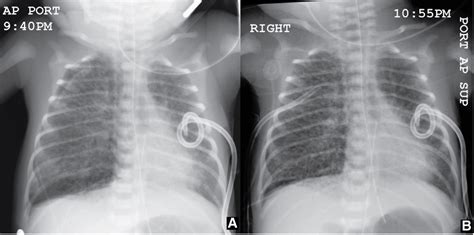

Okay, let’s get down to the nitty-gritty of how pulmonary interstitial emphysema radiology actually looks on a chest X-ray . This is often the first line of imaging used. When a radiologist looks at an X-ray of a patient with PIE, they’re scanning for specific patterns. One of the classic signs is the appearance of linear lucencies, which are essentially dark lines on the X-ray film. These lines represent air tracking within the interstitial tissues. Imagine tiny air bubbles or streaks running through the lung tissue, separate from the normal branching pattern of airways and blood vessels. Another key finding can be a ‘cystic’ or ‘bubble-like’ appearance, where larger pockets of air have accumulated in the interstitial space, sometimes looking like clusters of small balloons. You might also see signs of lung hyperinflation, where the lungs appear larger than normal, often because air is getting trapped. Sometimes, PIE can lead to a condition called pneumothorax, which is air in the space outside the lung, between the lung and the chest wall. This is a serious complication and appears as a dark space separating the lung from the chest wall on the X-ray. The diaphragm might also appear flattened due to the hyperinflation. It’s important to note that PIE can sometimes be subtle on an X-ray, especially in its early stages or if it’s mild. The radiologist has to be really vigilant and compare the current X-ray with previous ones if available to spot any changes. They’re looking for deviations from the normal, healthy lung pattern, and PIE creates a very distinct set of deviations. It’s a diagnostic puzzle, and the X-ray provides the primary pieces to solve it. The clarity and detail needed to spot these subtle linear lucencies and cystic changes are what make the radiologist’s expertise so vital in interpreting these seemingly simple images.